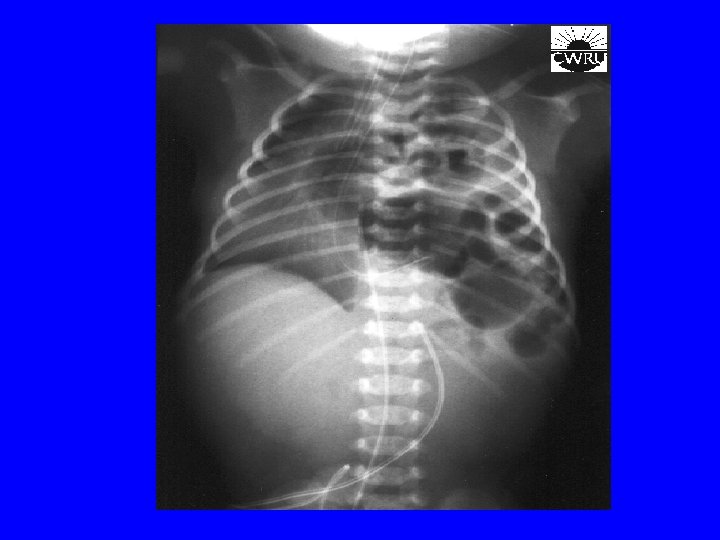

Congenital diaphragmatic hernia • Types: Posterolateral thru Foramen of Bochdalek (L>>R) and central thru Foramen of Morgagni • Clinically can present in-utero as hydrops, after birth as RD due to lung hypoplasia, scaphoid abdomen • Complications: related to lung hypoplasia and pulmonary hypertension (PH) • Treatment: IMMEDIATE intubation, correcting p. H and delayed surgical repair. May require ECMO